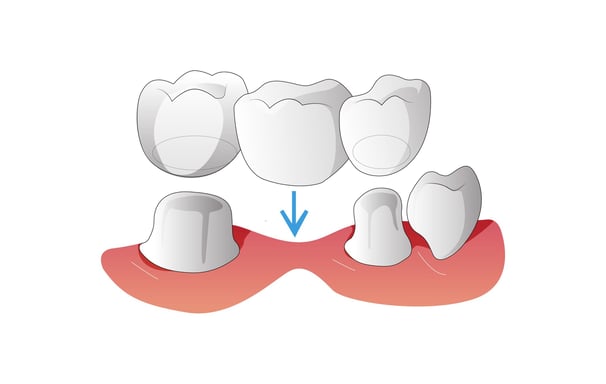

Los puentes reemplazan uno o más dientes faltantes mediante la unión de una prótesis entre dos coronas colocadas sobre dientes naturales o implantes adyacentes.

Puentes Dentales